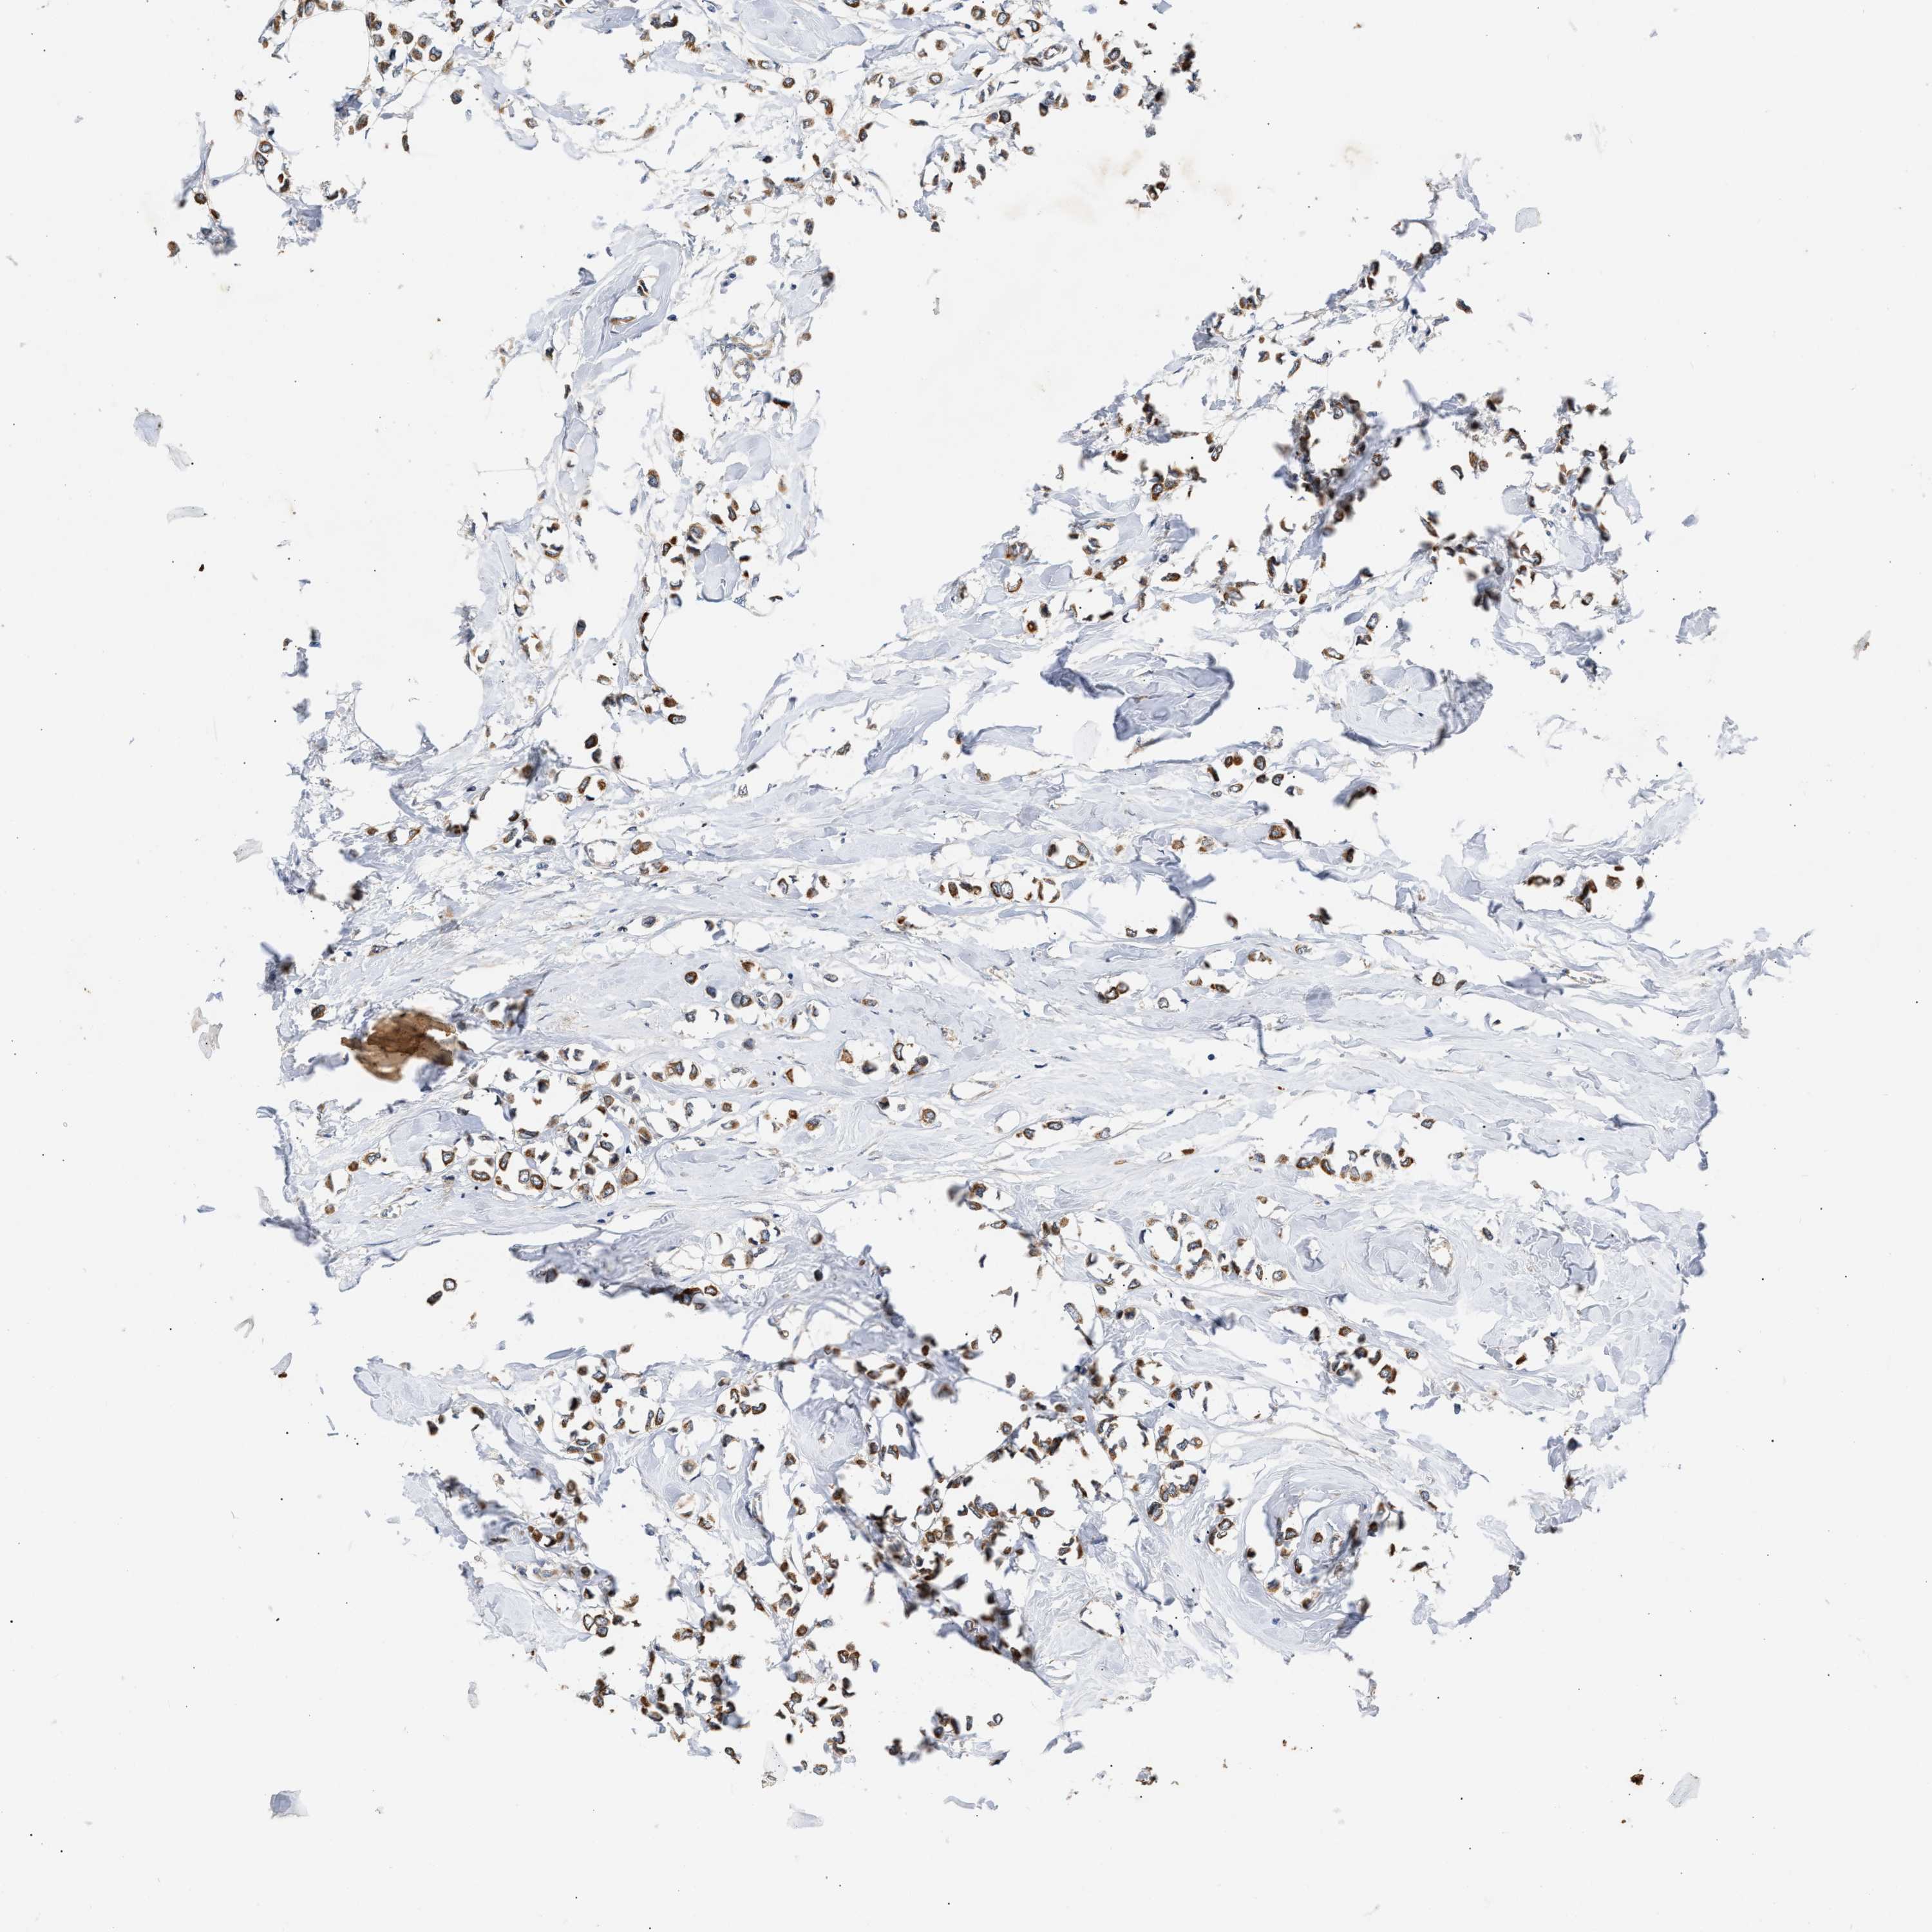

CANCER BREAST CANCER Show tissue menu

BRCA TCGA BRCA VALIDATION PROTEIN EXPRESSION

ANTIBODIES

AND

VALIDATION